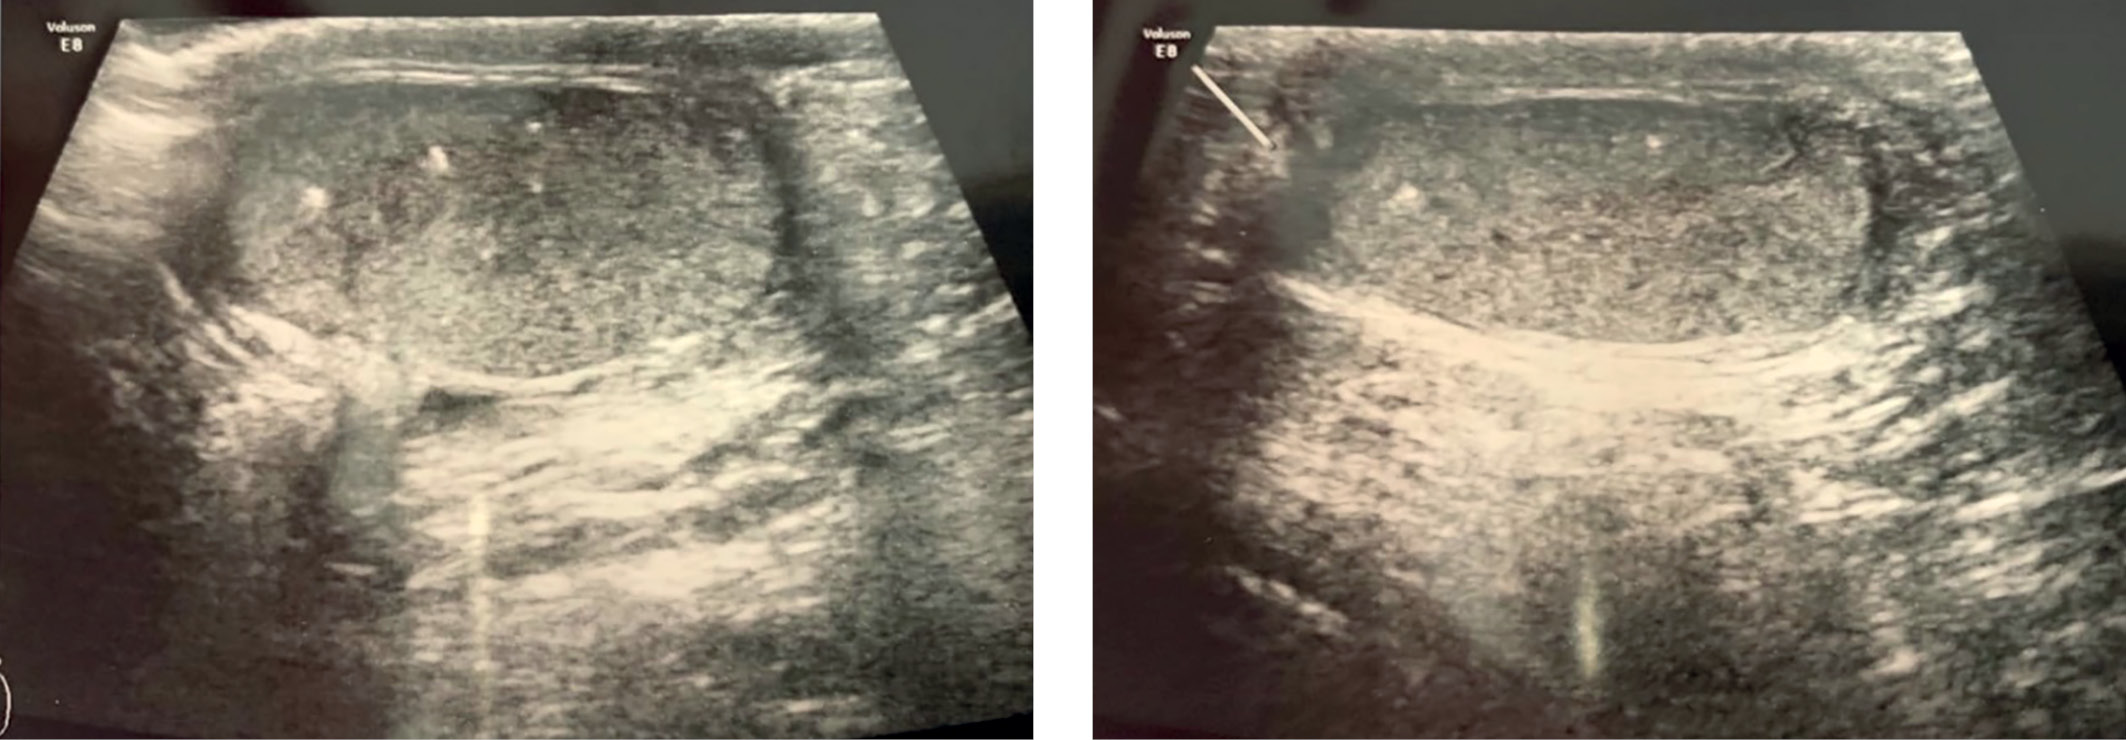

3. Figure 3. Ultrasound of the scrotum of patient F. | |